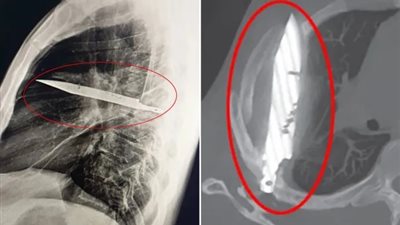

بعد شعوره بالألم.. أطباء يعثرون على سكين عالقة في صدر شخص منذ 8 سنوات

الخميس 14/08/2025 02:32 م